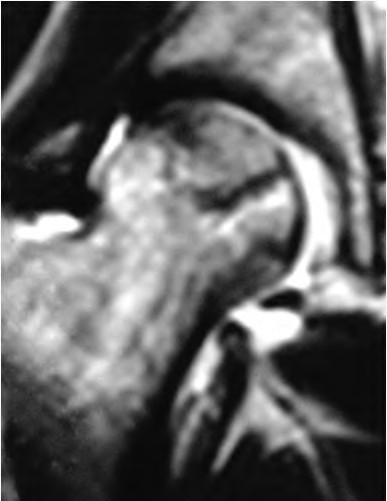

A 72-year-old female presents with progressive left thigh and knee pain for the last year. 5 years ago she sustained a femoral neck fracture treated with the implant seen in Figures A-C (current radiographs). The thigh pain is worse with weight-bearing. C-reactive

protein and erythrocyte sedimentation levels are within defined limits. Which of the following is the most likely cause of her pain?